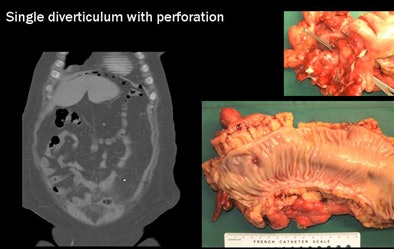

Importantly, "CT has the highest sensitivity for tiny air bubbles, which would not be detected on a conventional x-ray, ultrasound, or MRI," he said. "That's why CT is so important in this disease to detect the complications."

![]() |

| CT's most important advantage in imaging diverticular disease is its high sensitivity for air bubbles indicating colonic perforation. At left, bubble at CT reveals a single perforation in the colonic mucosa, confirmed in postsurgery specimen (right). |